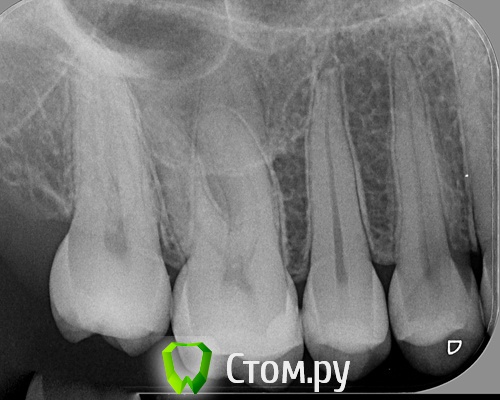

Korn05 Опубликовано 14 декабря, 2013 Поделиться Опубликовано 14 декабря, 2013 (изменено) Как лечить клиновидный дефект?Пломбу на его место поставили, пастами для чувствительных зубов пользуюсь, но боль продолжается (тянущая и слабая). Врач говорит, что не знает, что сделать.Прикрепляю снимок зуба (шестерка, второй слева) и фото (на фото клиновидный дефект немного виден, это вид до пломбирования). Изменено 14 декабря, 2013 пользователем Korn05 Ссылка на комментарий